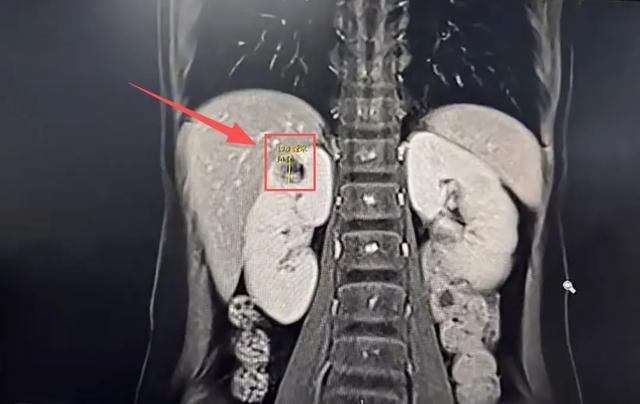

此后大半年里,他们辗转跑了好几家医院,北京也去了,来来回回折腾好几遍,终于在一次PET-CT检查中发现一个异常:

心心的右肾上,长着一颗很小的混杂性结节。

可让医生犯难的是:在B超检查中,这个“结节”更像是“囊肿”。

结合过往病史,周医生在超声报告上明确写上:考虑肾素瘤。